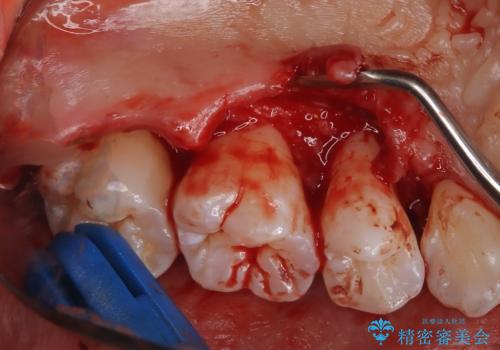

- 定期的にクリーニング(保険適応)に通って頂いている患者さんです。歯周ポケットが4ミリあったため歯茎を開いて歯石を除去するためにオープンフラップ術を行うことにしました。

歯周ポケットがそれほど深くない患者さんでしたが、いざ歯茎を開いてみるとそこにはたくさんの歯石がありました。もし歯周ポケットが4ミリだからと言って放置していれば数年後には、沢山の骨が無くなっていたことが予期出来ます。現段階で歯茎の下にある歯石を除去することにより骨が無くなることを予防する事が出来ました。